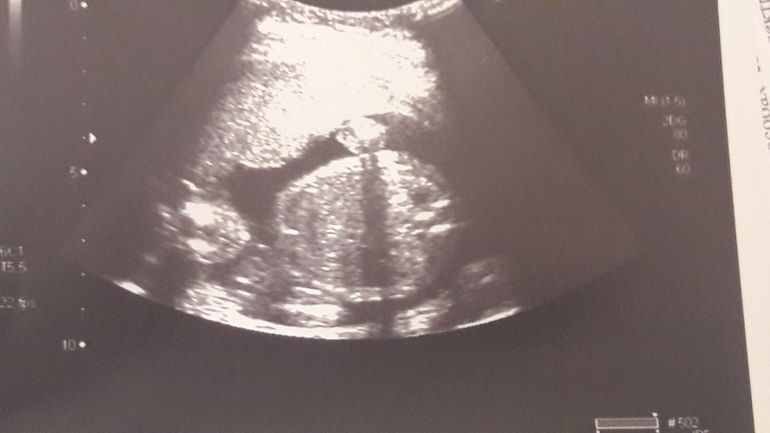

Мужу уже сюрпириз приготовила,ваш комментарий заставил засомневаться,думаю,сейчас мужа обрадую,а потом-бац-и принцесса.Пошла перепроверить в другую клинику.Дали вот такое фото

На этом фото не пойму ничего, но если сказали, что мальчик, то уж наверно точно теперь)